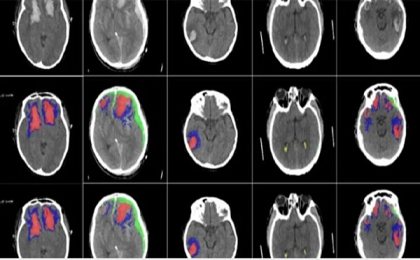

Các nhà nghiên cứu đã phát triển một thuật toán AI có thể phát hiện và xác định các loại chấn thương trong não.